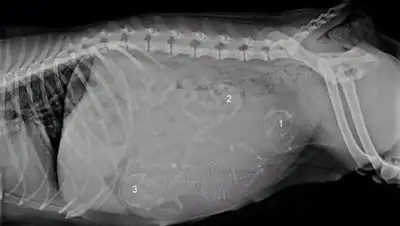

Собака